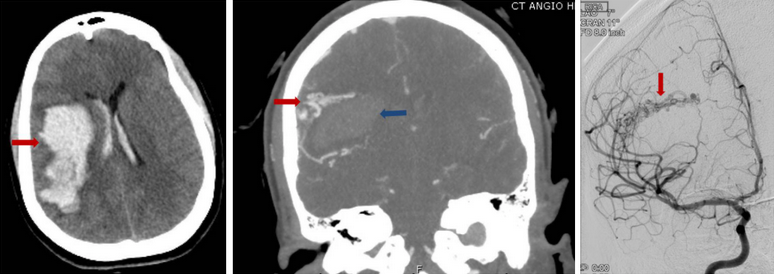

Brain arteriovenous malformations, or AVMs, are abnormal clusters of blood vessels within the brain. They are thought to arise during brain development in utero or shortly after birth. In these malformations, there are unusual connections between arteries and veins, which over time can weaken and possibly rupture. Read more…